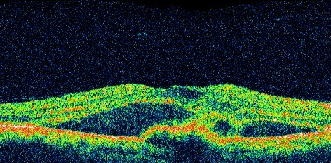

加齢黄斑変性の網膜断面図

滲出型の加齢黄斑変性では、網膜の外側にある脈絡膜から異常な血管(新生血管)が生じてきます。この血管はもろいため、血液成分が漏れたり、破れて出血を起こしたりして、網膜が障害を受けてしまいます。2009年に新生血管を抑える薬物(抗VEGF抗体)が認可され、目の中に直接注入する治療が一般に行われています。しかし抗VEGF抗体が有効でない場合は、レーザーと薬物を組み合わせた光線力学療法を行う場合があります。

加齢黄斑変性により黄斑が障害を受けると、視野の中心がぼやけたり、歪んで見えたり、暗くて見えにくくなったりして、視力が低下します。多くの場合、症状は片側の目からあらわれますので、異常に気づくのが遅れる場合があります。加齢黄斑変性には、進行が速い滲出型(しんしゅつがた)と進行が遅い萎縮型があります。加齢黄斑変性とよく症状が似た他の病気もあるので、早い段階で正しい診断を受けることが大切です。